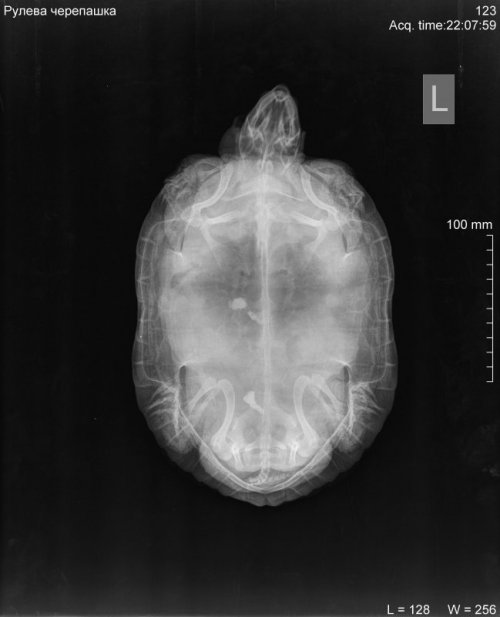

Podolnyi Ваше имя: Подольный Константин Локация: Украина, Днепр Опубликовано: 2 февраля 2020 Опубликовано: 2 февраля 2020 На рентгене просматриваются 3 контрастных конкремента, но мне не нравится характер их расположения. Нужно делать узд черепахи, через паховую ямку, для исключения фолликулярного стаза. Ибо на рентгене, как по мне, я вижу фолликулы на разных стадиях созревания. С большей долей вероятности, это петрификация(кальцинация) фолликулов. С правой стороны (возле таза) виден контрастный участок, я предполагаю это в устье яйцевода. Через клоаку пальпировали черепаху?

res23 Ваше имя: Екатерина Локация: Россия, Зеленоград Опубликовано: 5 февраля 2020 Автор Опубликовано: 5 февраля 2020 @Podolnyi Добрый вечер! Вот вернулись от доктора. Он нас успокоил, что ничего страшного нет, камушки где-то в кишечнике и должны сами выйти. Нижний вообще легко выйдет, верхний подольше. Фолликулы он сказал уже прошли максимум в своем развитии и идут на спад (не знаю, правильно ли я построила эту фразу...). Влил вазелинового масла. Чепушила буянила и далась только под каким то легким наркозом. Сделали укол Элеовита. Для контроля рекомендовано рентген недели через три. Ну а вообще Черепаха уже ведет себя практически как обычно и понемногу ест. Хотя еще надутая. Буду писать о наших успехах! Спасибо!

Podolnyi Ваше имя: Подольный Константин Локация: Украина, Днепр Опубликовано: 7 февраля 2020 Опубликовано: 7 февраля 2020 К примеру почему нужно очно смотреть такого рода проблемы. На фото представлен рентген черепахи и справой стороны компьютерная томография. На рентген видно, но крайне плохо, на кт, сами видите